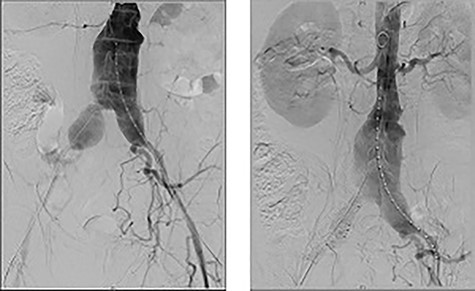

Urgent ureteric stenting to treat ureteric obstruction was performed with rapid normalization of renal function following stent insertion (Fig. 2). Upon normalization of his renal function, a contrast CT aortogram (CTA) was performed to delineate a 61 × 64 mm AAA, bilateral common iliac aneurysms (right 41mm × 44mm, left 31mm × 36mm) and associated peri-aortic stranding (Fig. 3).

CTA demonstrating (A) a large 61mm × 63mm infrarenal AAA and (B) bilateral common iliac aneurysms (right 41mm × 44mm, left 31mm × 36mm).